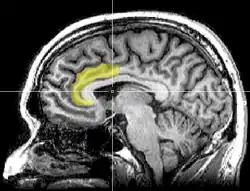

Physiology of self control

Unlike Freud's model where it was proposed that the energy for self control just came from "within" there is supportive research showing the areas of the brain that are linked to self control. It mainly happen from within the prefrontal cortex, in areas such as the anterior cingulate cortex.

Although all areas of the brain require blood glucose to function, there are certain areas that are more sensitive to the flow of glucose through the brain. Responses that require more effort or are a controlled response will require more glucose, same with higher executive functioning. This also explains why the whole brain does not stop working once the glucose falls, such as with self control, if an automatic, less effortful response is less sensitive to blood glucose, it will not stop functioning if there is a drop in glucose levels. However, these functions can not be over stimulated with excess glucose to produce some super self control (Galliot & Baumeister, 2007)